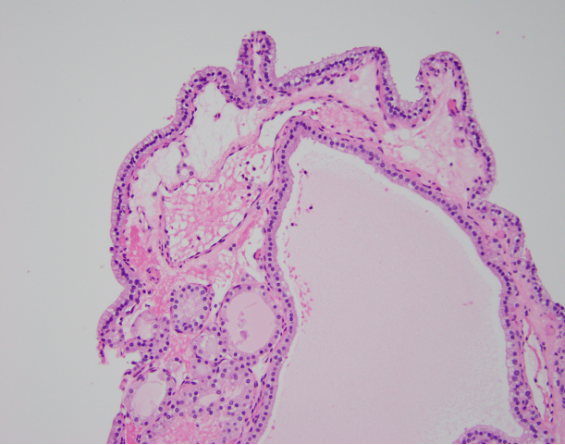

First image: FA with pap architecture. On high power the cells are often columnar. The nuclei are basally located and are small, round, and dark. Nuclear features of papillary thyroid carcinoma are always absent. The edematous fibrovascular cores show embedded follicles.

Below image; Follicular adenoma with papillary architecture - Low power view showing large colloid-filled follicles and complex papillary infoldings of the lining epithelium.